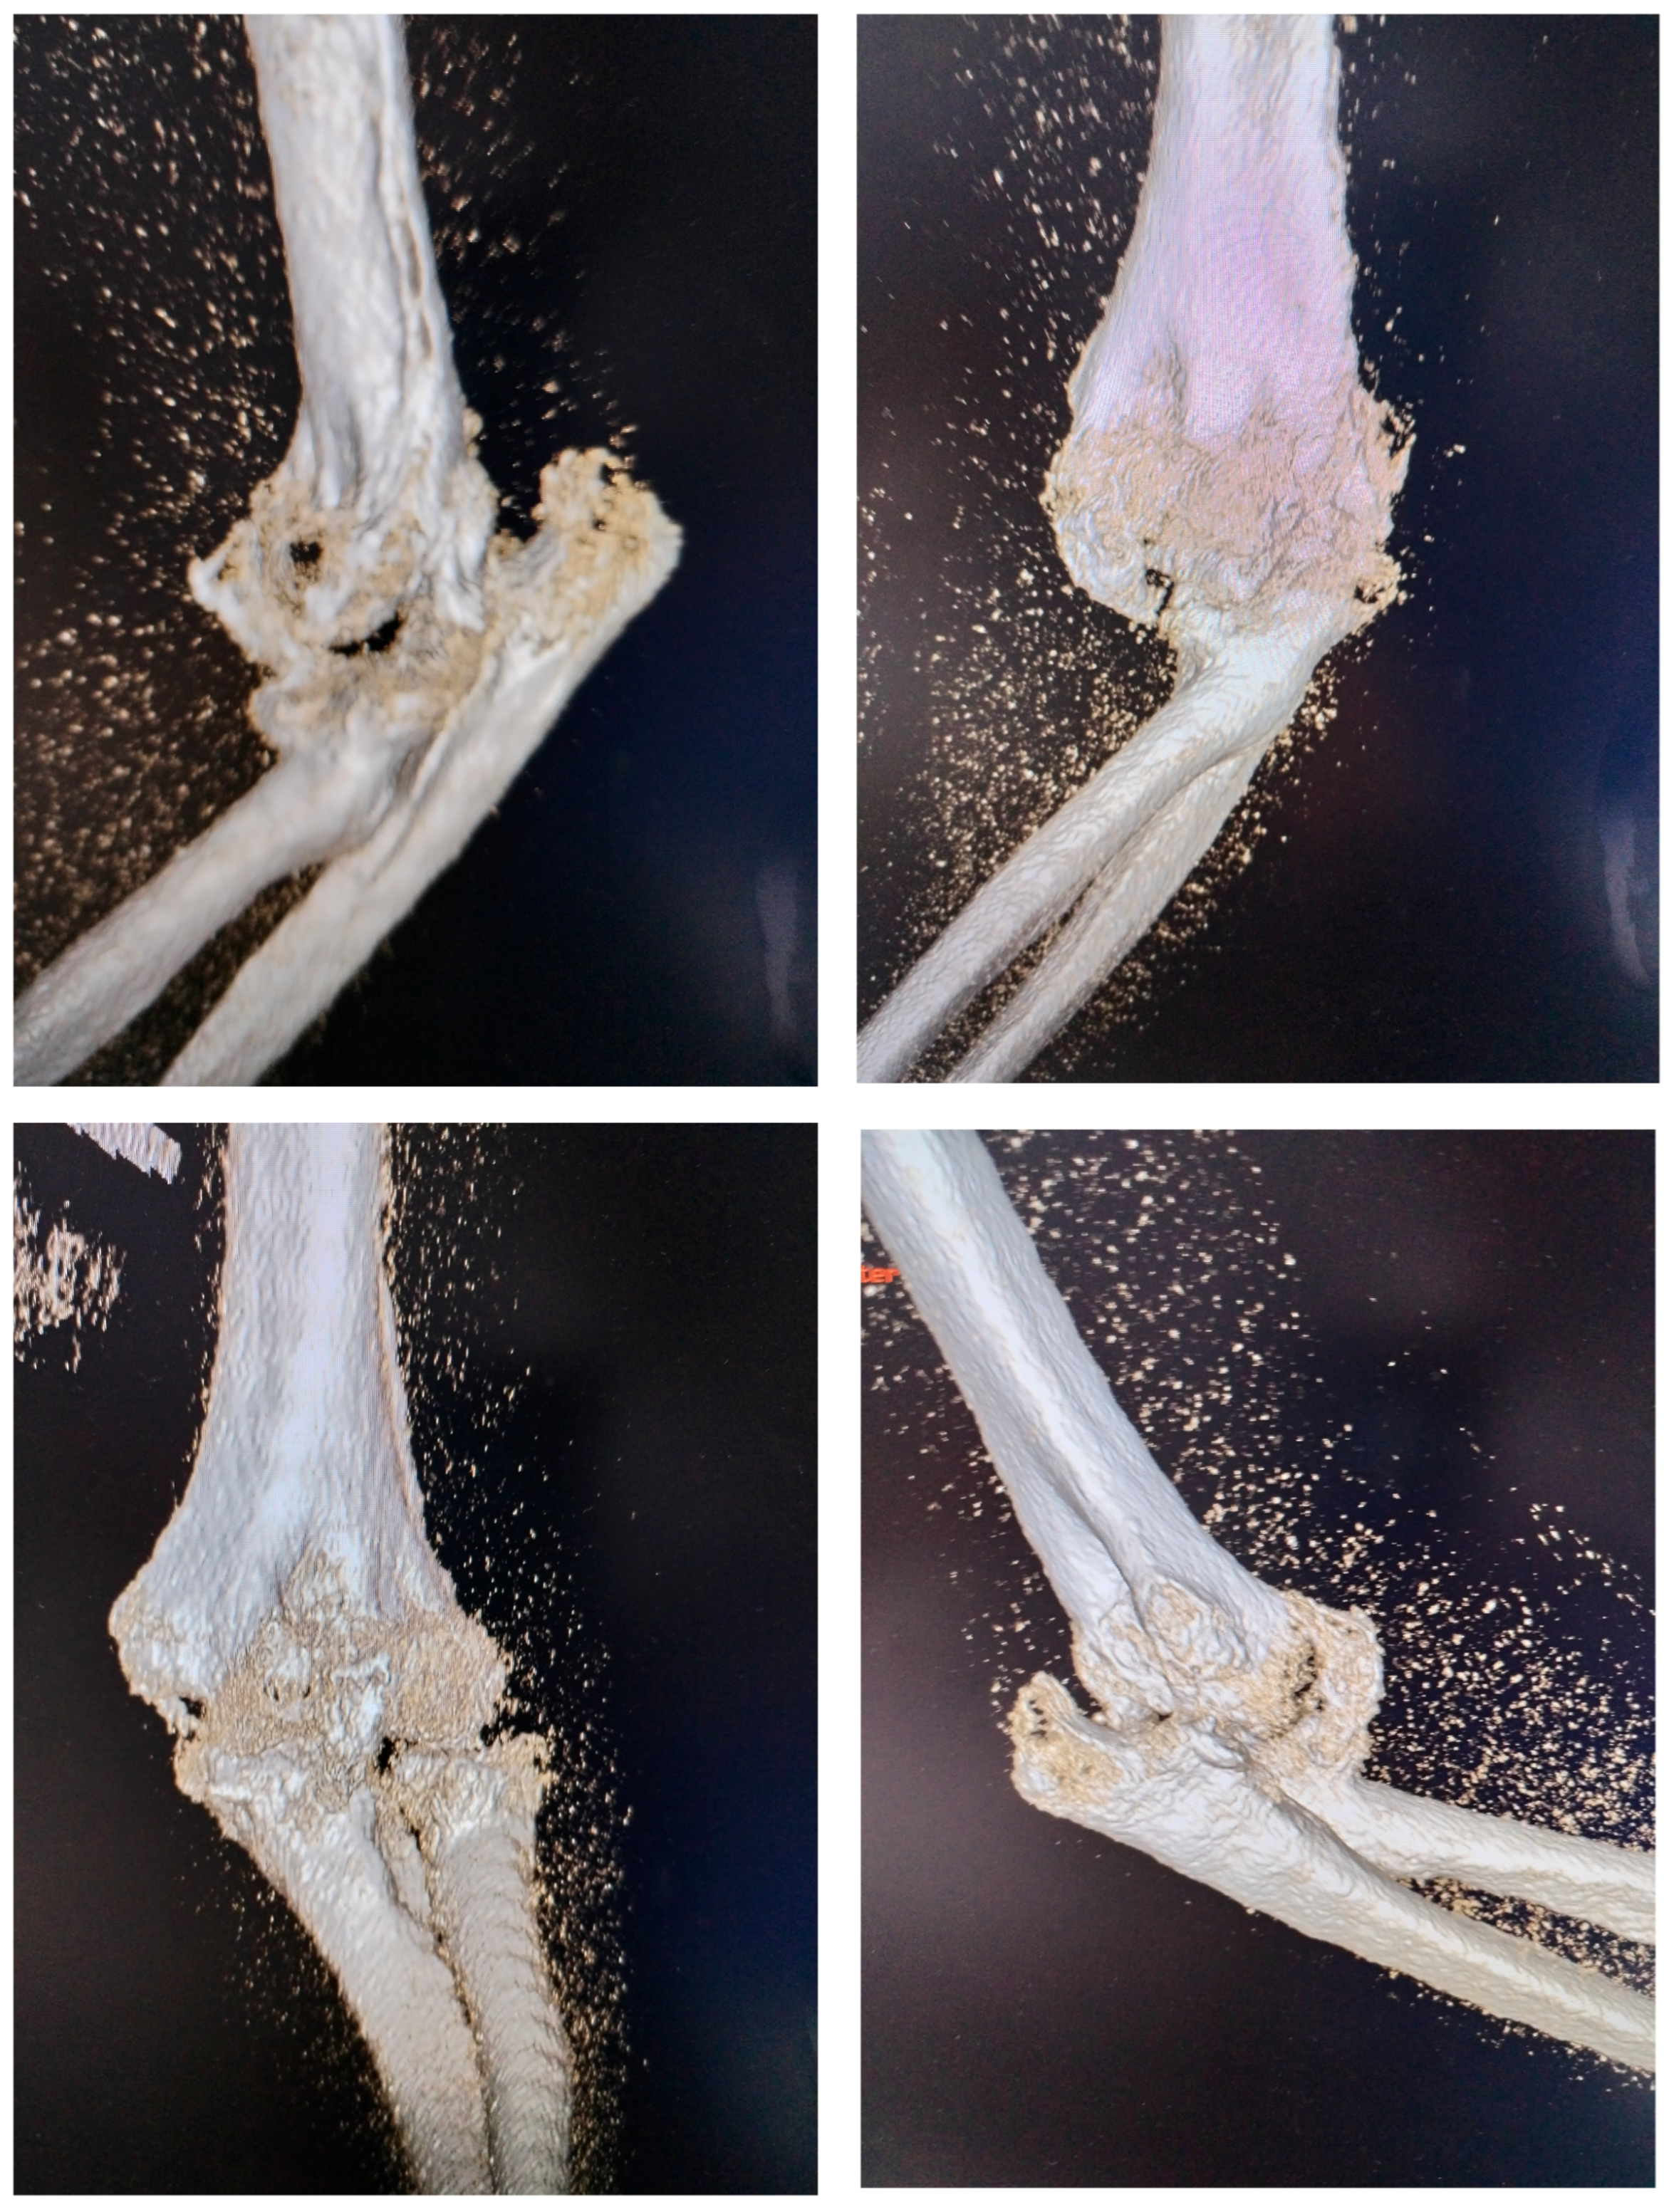

At the time of the injury, the posterior elbow dislocation with associated fractures was not fully diagnosed. The patient initially underwent closed reduction and cast immobilization, but the original radiographs taken immediately after the trauma and following the first reduction were unavailable. Radiographs obtained at the time of admission to our clinic were inconclusive due to extensive heterotopic ossification, prompting a 3D computed tomography (CT) scan to better visualize the bony anatomy and the joint relationships (Figure 2). The CT scan revealed a chronic posterior elbow dislocation with a large heterotopic bone mass within the joint. The coronoid process of the ulna was no longer discernible, suggesting resorption or fragmentation at the time of injury. The radial head was severely deformed (Masson 3), preventing normal articulation with the capitulum and functionally blocking the proximal radioulnar joint.

Figure 2. 3D CT aspect with visualisation of dislocation and presence of a massive heterotopic bone inside the joint.